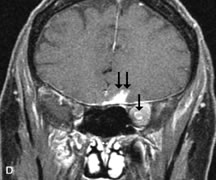

Intraorbital and intracranial optic nerve sheath meningiomas are usually isointense to cortical gray matter on Tl-weighted images and remain isointense on proton density studies (Fig. 15). Gd-DTPA is useful in delineating the intracranial extension of optic nerve meningiomas.7,47 The hyperostosis of bone and calcification associated with meningiomas are not demonstrated as well on MRI studies as on CT scans.20,37 Gd-DTPA–enhanced MRI also appears promising in the study of the permeability of the blood–brain barrier in selected optic neuropathies.22,48 MRI may reveal an enlarged optic nerve and some degree of contrast enhancement in cases of optic neuritis.49

Fig. 15. A. T1- and (B) T2-weighted MR scans demonstrate a mass causing fusiform enlargement of the optic nerve sheath complex. The peripheral portion of the mass, representing the meningioma, is isointense to brain on the T1-weighted scan and notably hypointense on the T2-weighted scan. The central portion of the mass, representing an edematous optic nerve, is very hyperintense on the T2-weighted scan (arrow), C and D. Postcontra fat-suppressed T1-weighted scans demonstrate intense peripheral enhancement of the meningioma surrounding the central nonenhancing optic nerve (arrow). Also note the enhancing Intracranial “dural tail” (double arrow).